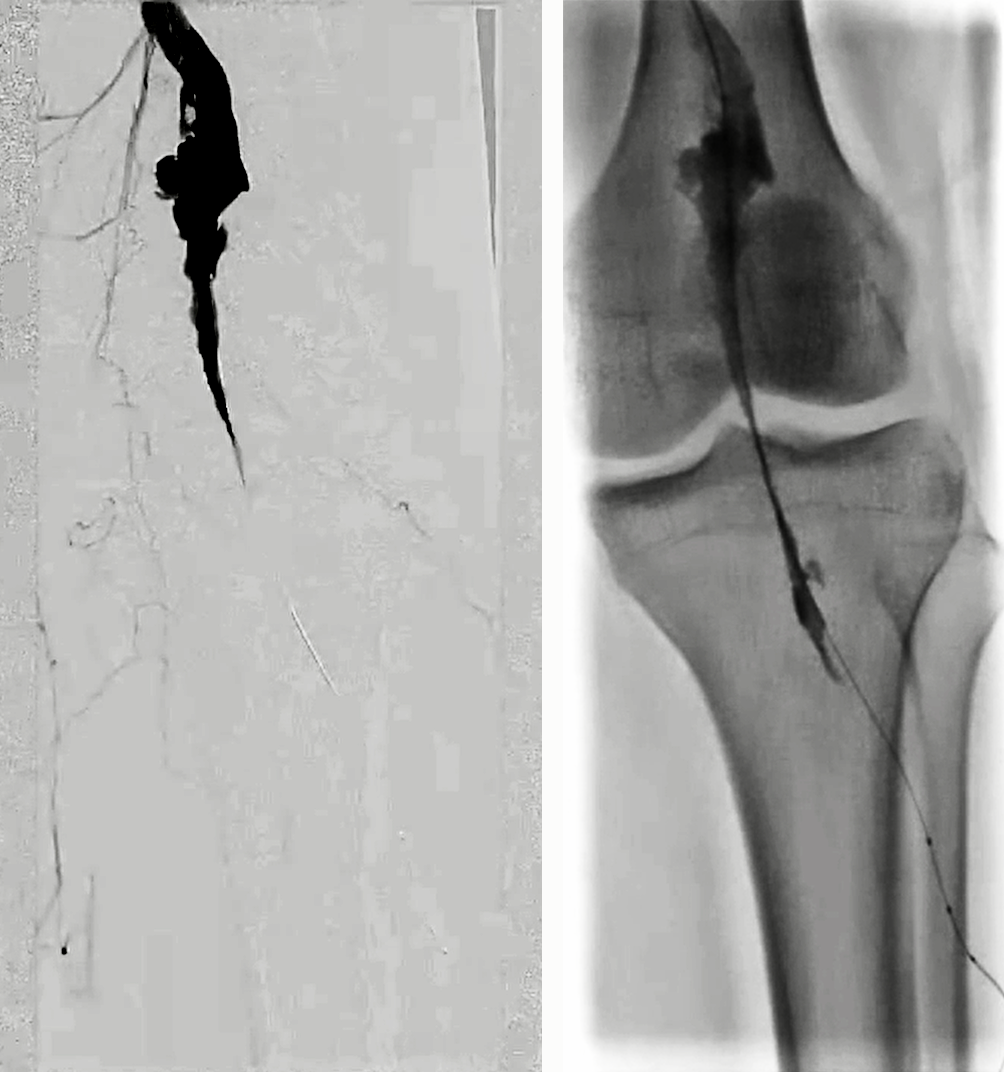

5. 路图下4mm×200mm球囊扩张自腘动脉远端至假性动脉瘤上端,4个大气压时患者诉疼痛。造影见腘动脉未显影;

6. 将导管向远端推送跨过动脉瘤,造影见腘动脉P1P2交界处血管破裂,远端仍未显影;将导管推送至P2段,见造影剂外溢和远端夹层形成;

7. 造影发现腘动脉末端1cm可作为覆膜支架远端锚定区;自腘动脉末端至P1段置入5mm×100mm Viabahn;序贯置入7mm×100mm和7mm×50mm Viabahn,近端至内收肌管口水平,覆盖一个侧枝;6mm×200mm球囊后扩;